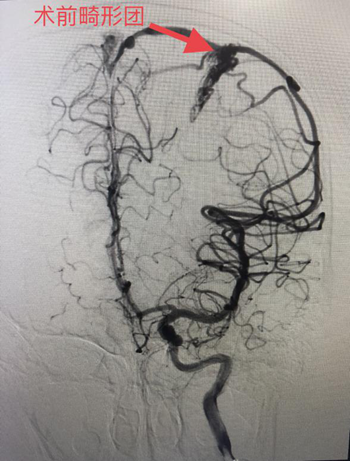

(术前造影图)                     (术后造影图)

近日,廖驭国团队成功抢救一名动静脉畸形破裂出血的14岁儿童。该患者经外院紧急转送至我院,入院时神志嗜睡,外院CT提示左侧颞顶叶急性脑出血。神经外科首诊医生廖军研判,患者高度疑似颅内动静脉畸形破裂出血,“时间就是大脑”情况十分紧急,急需手术治疗,马上汇报神经外科主任、神经介入中心主任廖驭国同时向家属解释病情并经得同意后,在麻醉科医生精准麻醉和严密检测下,廖驭国带领神经外科李海堃副主任医师为患者进行颅内动静脉畸形栓塞术,术中完美栓塞畸形团,顺利完成手术。